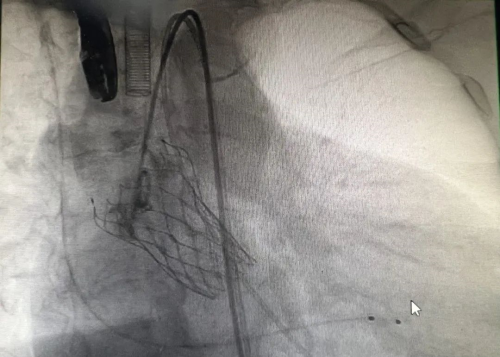

经过充分的准备,7月30日,手术在导管室内顺利进行。在麻醉医师的精心操作下,超声科医师迅速置入食道超声以监测手术进程。杨继承主任医师带领的心胸外科医师团队凭借高超的技艺,在严爷爷左右股动脉处各开一微小切口,随后在导丝引导下,成功将人工瓣膜送达主动脉瓣位置并完美释放。术后,严爷爷的血流动力学立即得到显著改善,各项生命体征平稳。